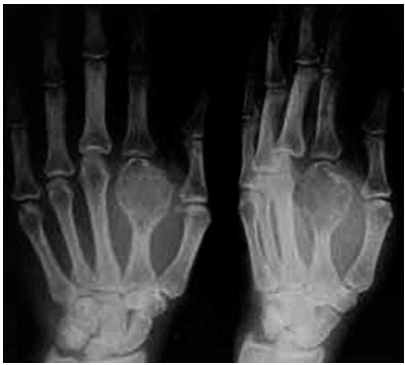

Radiographs of GCRG usually show a lytic, expansile lesion in one of the phalanges or metacarpals with no evidence of cortical invasion or periosteal reaction, but aggressive variants have been described.

The most common preoperative radiographic diagnosis has been enchondroma, GCT and Aneurysmal bone cyst (ABC). While the location and the expansile nature of the lesion are compatible with enchondroma, GCRG does not exhibit calcification of the matrix. Moreover, the demarcation between abnormal and normal bone is less well defined than in typical enchondroma. ABC is rarely located in the small bones of the hands and feet. Unlike ABC, the majority of the lesions in GCRG occur after closure of the epiphyseal plate.

GCT is the most difficult to distinguish from GCRG; it affects the same age group as GCRG and has similar radiographic signs, except, it is typically more aggressive. Wold LE and Swee RG and colleagues 9, 10 also noted that the clinical and radiologic features did not distinguish between the 2 entities, and a history of trauma was inconsistent.